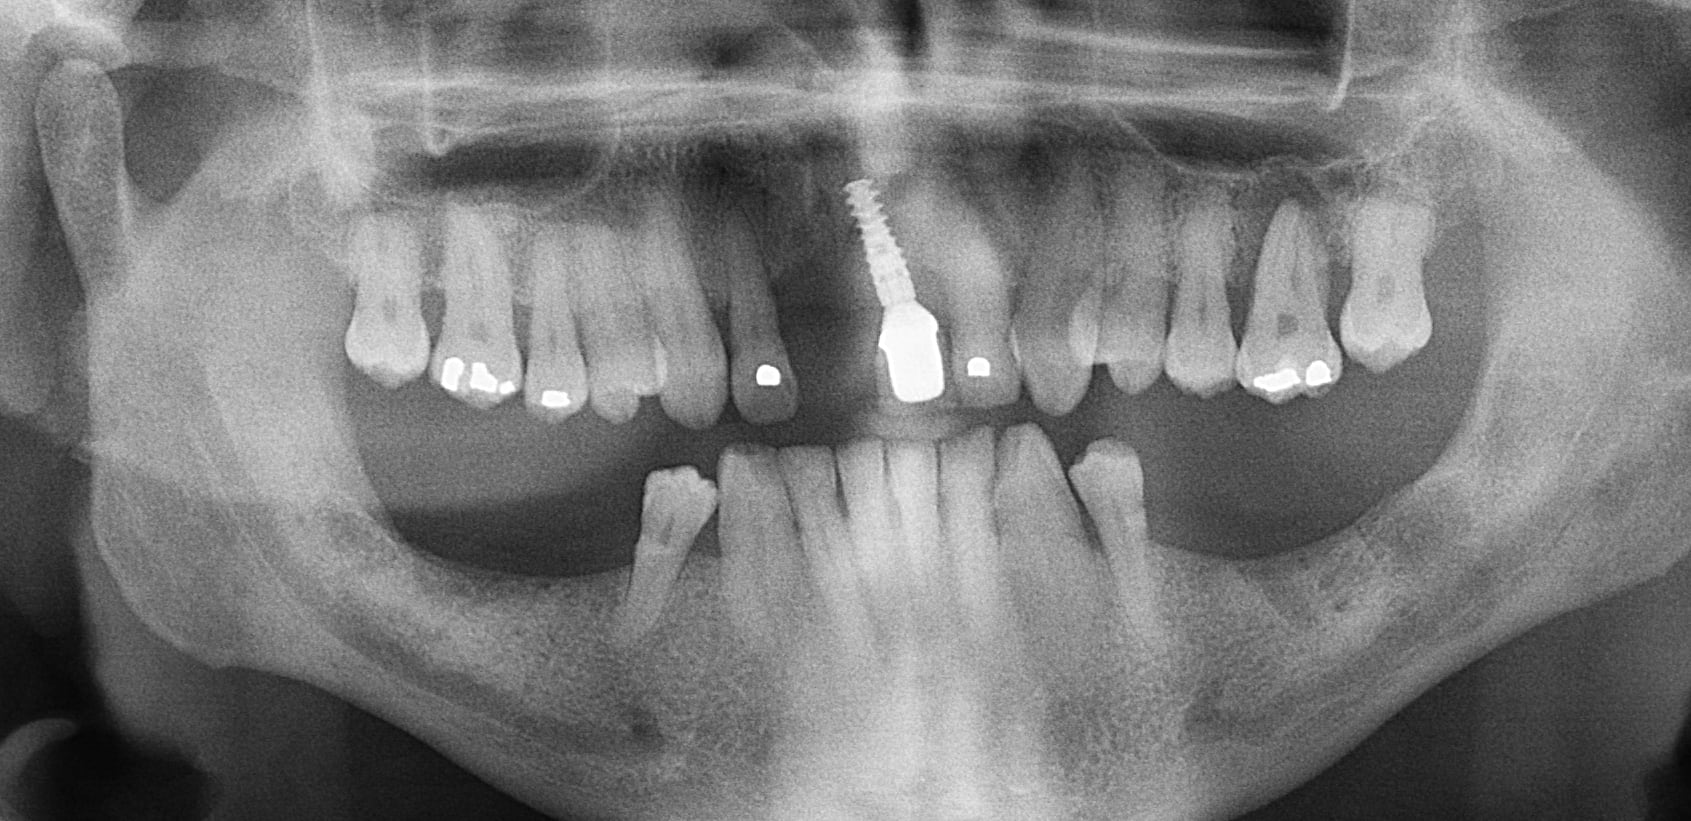

Patient d'une petite soixantaine d'années. Brossage correct et brossettes. Pas de prothèse inférieure.

Il y a un "contrat" sur la 26, pas sur les voisines. Et il ne fallait pas mettre d'implant pcq la zone 11-21 est électriquement anormale. Perdu d'avance.

Cette hypothèse électrique permet peut-être de comprendre pourquoi cette dent couronnée il y a 25 ans est asymptomatique. Le cône distal est mobile, mais pas le lentulo.

Pour le 1er cas les extractions en bas datent d'il y a plus de 20 ans.

Les radios postées peuvent bien entendu permettre beaucoup d'interprétations.

La 26 égressée m'interpelle pcq les autres n'ont pas bougé alors quelles n'ont pas d'antagonistes non plus depuis longtemps.

L'interprétation d'enlaye est tout à fait possible, mais elle ne me satisfait pas pcq je ne peux pas expliquer par exemple des déplacements dentaires mésio-distaux de dents sans antagonistes et parfois sur plusieurs mm.

Bien d'accord junior, mais le calage se fait sur les 4 depuis 20 ans et les latérales, moins bien plantées que les centrales en principe, ne se portent pas trop mal.

Je suis entièrement d'accord avec toi, mettons lui des dents en bas, mais je me dis quand même que c'est bizarre que les latérales ont tenu le coup. L'implant tient toujours très bien sur les 2 ou 3 mm qui restent. La centrale n'est pas en contact avec son antagoniste, mais bon, ça ne va sans doute pas évoluer favorablement...

Pourquoi à ton avis il y a plus de perte d’os sur l’implant au niveau de l’incisive ? C’est tout à fait normal qu’on constate une telle perte osseuse . Trois facteurs sont en cause ici : l’occlusion (pas de calage) la parodontite , plus la pose de l’implant (son orientation) . D’autant plus que l’incisive centrale est d’avantage utilisée qu’une incisive latérale. Surtout qu’on le sait tous : si il y a eu pose d’implant ça veut dire qu’il y a eu extraction. Qui dit extraction dit perte d’os . Donc déjà dans cette zone on avait moins d’os en verticale et en épaisseur . Sauf si le dentiste a reconstruit une épaisseur osseuse ou fait une expansion, ce que je doute fortement. Donc déjà faut partir du principe que l’implant ait été posé dans un os moins épais que ce qu’on trouve au niveau de ses latérales par exemple.

Et sans parler de l’orientation de l’implant ! Est-ce qu’il a été posé dans l’axe de la centrale ? J’en ai pas l’impression . Faut pas s’ étonner si on a plus d’os perdu sur un implant posé obliquement et dont l’axe a été rattrapé par le pilier et la couronne. Déjà on sait que le mec n’a pas posé ça correctement dans le sens horizontal. Alors je n’ose pas imaginer dans le sens sagittal comment ça a été posé :) .